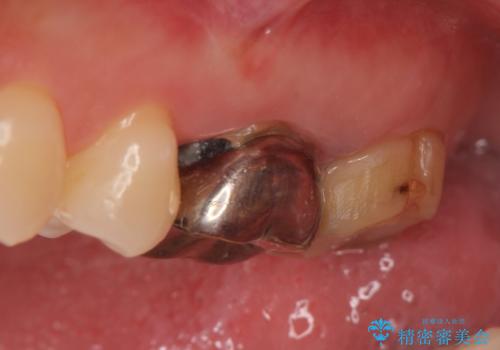

- 他院にて治療した左上奥歯の疼くような痛みが引かないため当院にいらっしゃった方の症例です。

検査の結果左上6に打診痛、根尖部圧痛、根尖病変を認めたため、再根管治療を行ったところ症状が緩解したため、オールセラミッククラウンによる補綴を行いました。

左上7は治療を希望されなかったため、オールセラミッククラウンによる補綴のみを行いました。